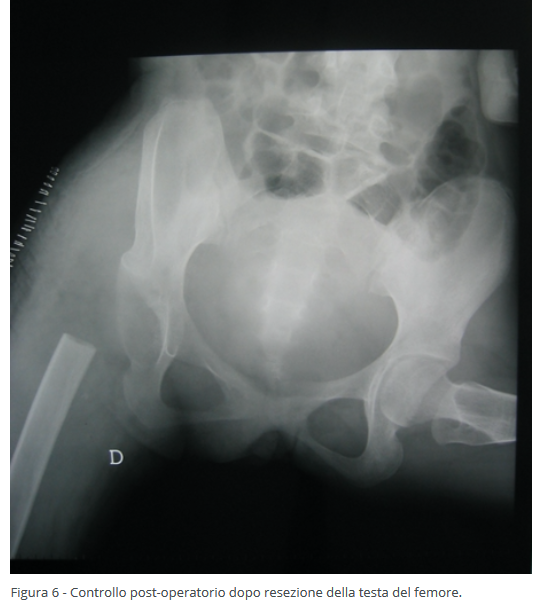

Il terzo livello di trattamento chirurgico delle deformità dell'anca nei bambini con paralisi cerebrale infantile avviene sul femore nei pazienti più grandi in cui non è più possibile ricondurre la testa del femore all'interno dell'acetabolo. Tale intervento prevede la resezione e l'asportazione della testa del femore in modo da non avere più attrito tra testa del femore  e bacino. Questo intervento si esegue in genere sopra i 15 anni di età, permette la risoluzione completa del dolore e il recupero dei movimenti della coscia (Figure 5-6).